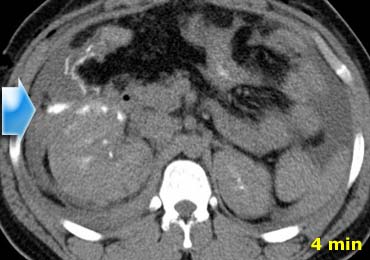

Chấn thương xuyên thấu

Hãy quan sát các hình ảnh bên trái và cố gắng trả lời các câu hỏi sau:

- Vai trò của CT ở bệnh nhân chấn thương xuyên thấu là gì?

- Các dấu hiệu hình ảnh là gì?

Đáp án:

- Vai trò chính của CT là xác định xem có vi phạm phúc mạc hay không và dự đoán nhu cầu phẫu thuật mở bụng

-

Các dấu hiệu hình ảnh:

Trong pha mạch máu ở phút thứ 1, có hiện tượng thoát thuốc cản quang và dịch trong các rãnh cạnh đại tràng, cho thấy vi phạm phúc mạc.

Ngoài ra còn có khối máu tụ trong khoang quanh thận. - Trong pha muộn, có thêm hiện tượng thoát thuốc cản quang, mặc dù chưa rõ liệu đó là do chảy máu tích cực hay thuốc cản quang thoát ra từ hệ thống thu thập nước tiểu

- Trong pha bài tiết, rõ ràng có sự vi phạm hệ thống thu thập nước tiểu